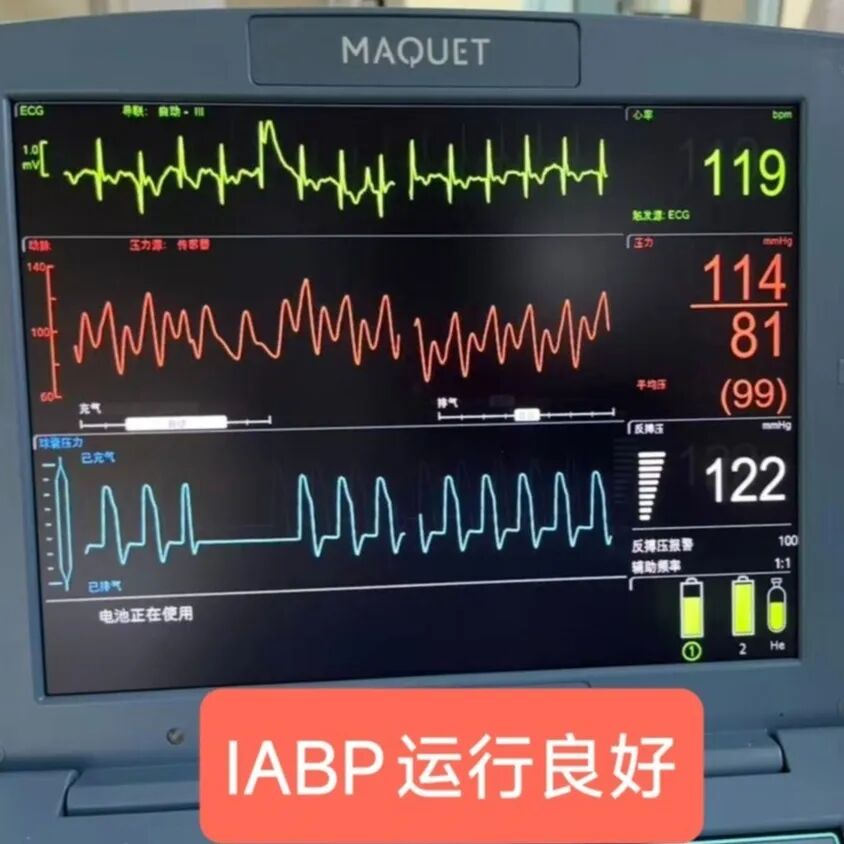

在疏通血管的过程中,钟先生还出现了血压下降、呼吸困难等危险情况。关键时刻,团队紧急启用IABP技术,李驹植入IABP球囊,改善冠状动脉血流,稳住患者血压,为营救患者争取时间,之后迅速植入支架,开通血管,稳定钟先生心脏血液循环。经过近3小时的紧张手术,钟先生的堵塞血管成功疏通,生命体征逐渐稳定,随后转入危急重症中心(ICU)进一步治疗。

IABP将球囊植入主动脉,植入后IABP显示球囊运行良好

李驹指导进行IABP调试